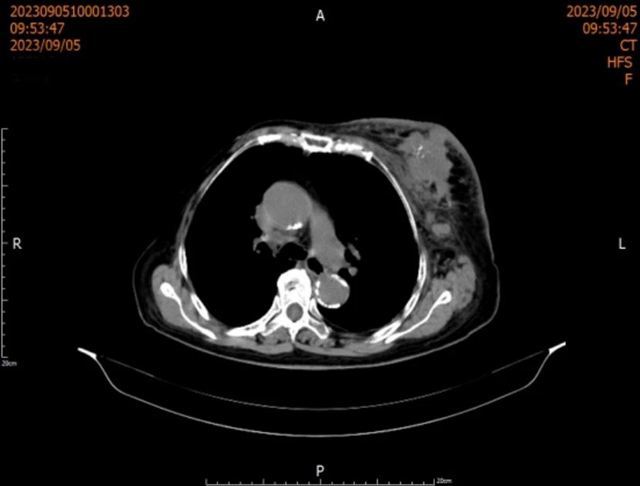

入院后,通过颅脑+颈部+胸部+全腹部增强CT检查,结果提示恶性肿瘤性病变,并有转移。

经过两周期治疗后,对比上次检查结果看:左侧乳腺区肿块减小,左侧腋窝、锁骨上窝区淋巴结减小;右肺上叶结节吸收。